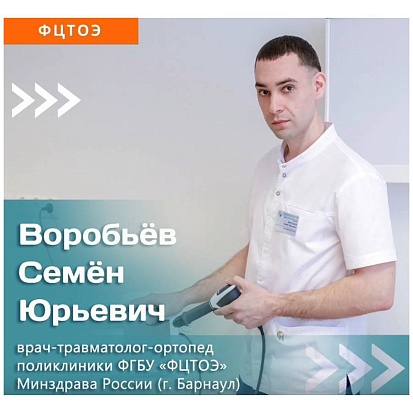

Ударно-волновая терапия

Ударно-волновая терапия